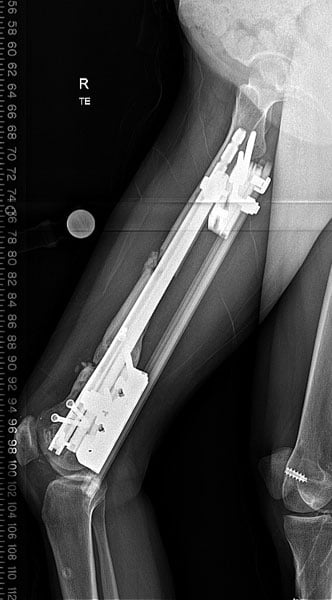

Dr. Fragomen performed surgery to lengthen the femur and correct the bowing deformity. He did this by cutting the femur bone in two places and inserting a rod to hold the bone straight. An external fixator was then used to gradually stretch the bone longer letting it slide over the internal rod.